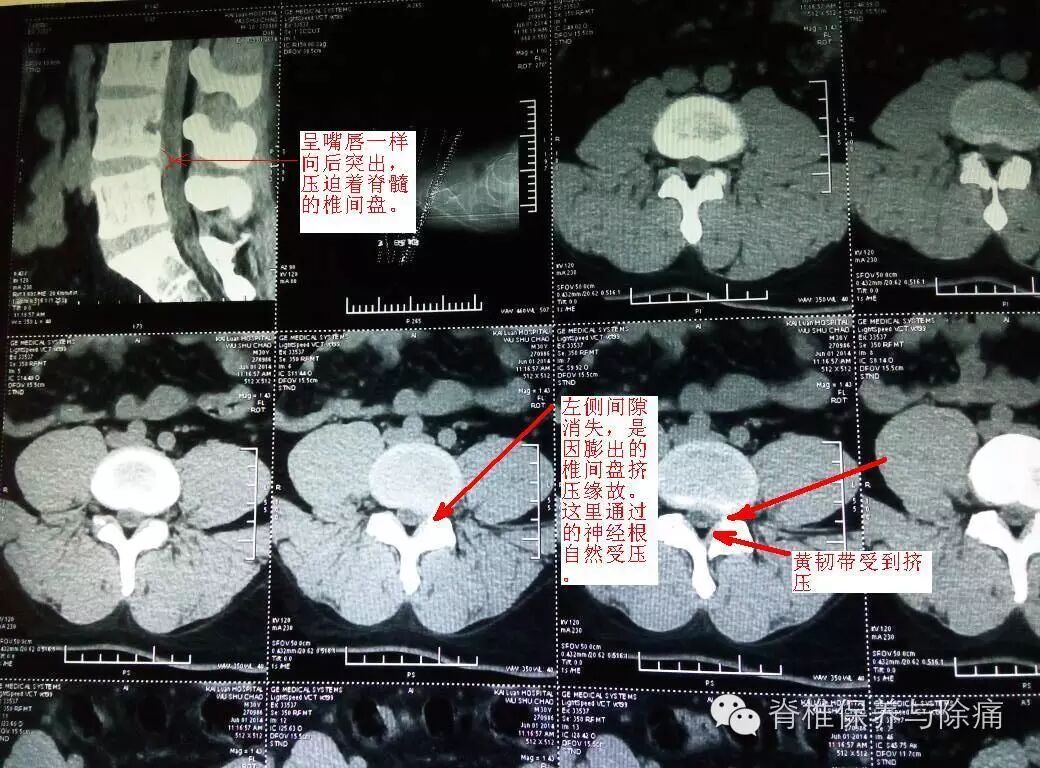

病例1

L4/5椎间盘呈唇样影后突(偏左侧),左侧侧隐窝变窄,硬膜囊外脂肪略受压。